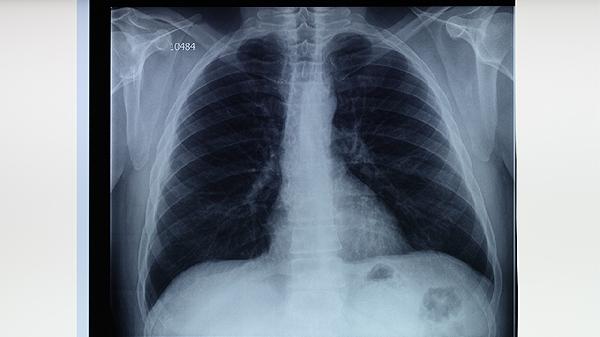

中央型肺癌可能引起持續(xù)性咳嗽、痰中帶血,與肺結(jié)核空洞型病變癥狀重疊。但肺癌多見(jiàn)于中老年吸煙人群,胸部CT可見(jiàn)分葉狀腫塊,腫瘤標(biāo)志物可能升高。肺結(jié)核患者結(jié)核菌素試驗(yàn)多呈強(qiáng)陽(yáng)性,痰培養(yǎng)可鑒別。臨床常用吉非替尼片、注射用培美曲塞二鈉、卡鉑注射液等抗腫瘤藥物。

肺膿腫患者可出現(xiàn)高熱、咳大量膿臭痰,與肺結(jié)核繼發(fā)感染時(shí)相似。但肺膿腫多有誤吸史或牙周疾病,CT顯示空洞伴液平面,痰培養(yǎng)以厭氧菌為主。肺結(jié)核空洞多位于上葉,痰抗酸染色陽(yáng)性。治療肺膿腫常用甲硝唑氯化鈉注射液、注射用哌拉西林鈉他唑巴坦鈉、鹽酸莫西沙星片等。

支氣管擴(kuò)張表現(xiàn)為長(zhǎng)期咳嗽、咳膿痰,易與慢性纖維空洞型肺結(jié)核混淆。但支氣管擴(kuò)張患者多有幼年呼吸道感染史,高分辨率CT可見(jiàn)支氣管囊柱狀擴(kuò)張,痰培養(yǎng)無(wú)結(jié)核菌。肺結(jié)核患者多有接觸史,影像學(xué)可見(jiàn)樹(shù)芽征或鈣化灶。支氣管擴(kuò)張急性期可用吸入用布地奈德混懸液、鹽酸氨溴索口服溶液、阿奇霉素分散片等。